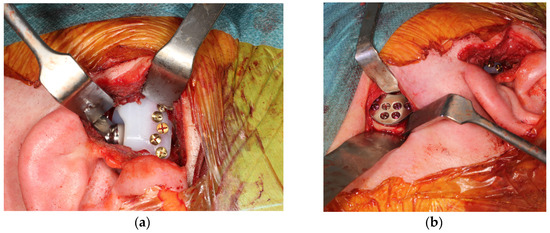

2.3.2. Surgical Procedure